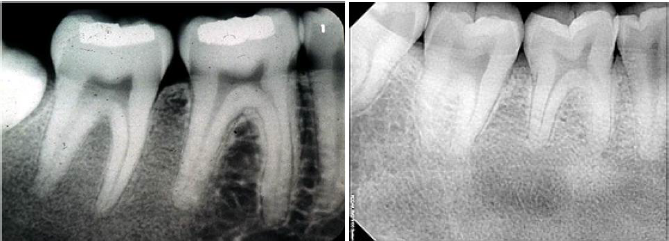

idiopathic osteosclerosis

a focal area of increased bone density that cannot be attributed to any specific cause

common

also seen in other bones

teens and young adults

mandible (90% of cases) : premolar and 1st molar area

adjacent teeth are vital

idiopathic osteosclerosis differential diagnosis

contrast with condensing osteitis

if the tooth is non vital - condensing osteosis

condensing osteitis

features of condensing osteitis

non-vital tooth or presence a source of inflammation

widened PDL

sclerosis of bone around roots in response to chronic inflammation

may mimic idiopathic osteoscerosis